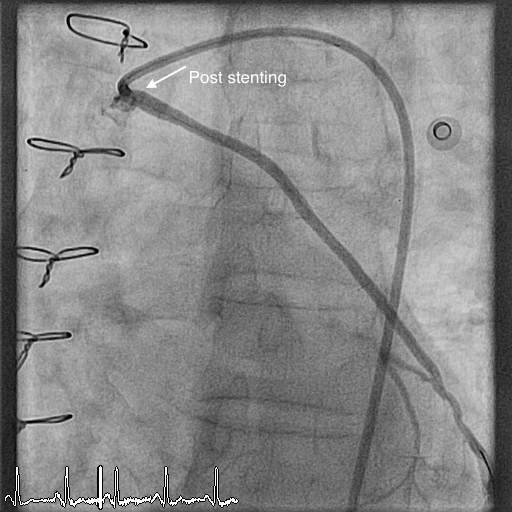

Vein grafts are used during bypass surgery to bypass the blood flow through narrowed coronary arteries. These are mostly taken from leg and used in the heart. Over a period of time, the vein grafts itself can get narrowed and cause chest pain. An angiogram of the graft will confirm this and this may require intervention in the form of angioplasty. Vein graft angioplasty is challenging, as the walls of veins are different from arteries. There is also high risk of clots going down the graft during ballooning process. This requires expertise and also special devices to prevent this happening and to get good result from angioplasty.